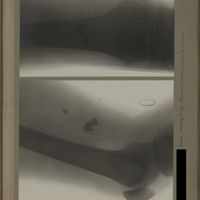

0167 - Page 55 - [Radiographie du bassin]0167 - Page 55 - [Radiographie du bassin]

0128 - Page 16 - [Radiographie du bassin]0128 - Page 16 - [Radiographie du bassin]

Table des matières